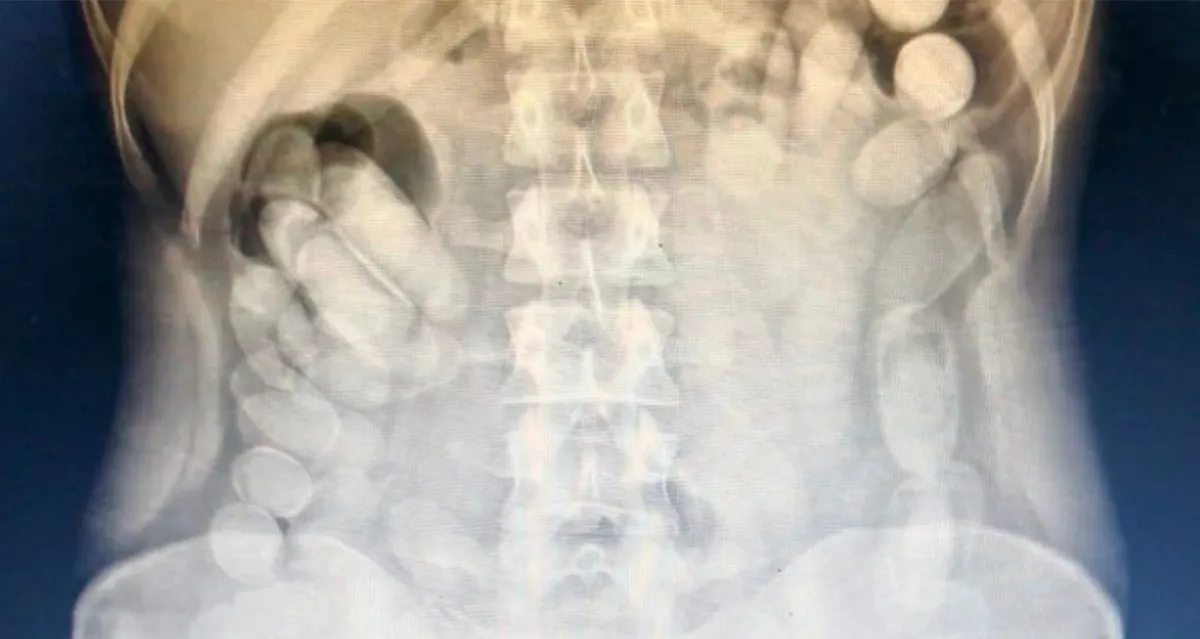

Una mujer fue detenida por Gendarmería Nacional durante un operativo de control fronterizo en la localidad tucumana de Trancas. El procedimiento ocurrió el lunes en el paraje Molle Yaco, cuando efectivos revisaban un colectivo de larga distancia. Durante la inspección, detectaron que una pasajera llevaba bolsitas con cocaína en su bolso. Al continuar con la requisa, notaron que también ocultaba cápsulas dentro de su cuerpo. En total, llevaba 106 cápsulas de cocaína. Fue trasladada al Hospital Centro de Salud para estudios médicos y permanece internada.

Ya en el Hospital Centro de Salud de la capital tucumana, los estudios radiológicos confirmaron lo que temían: llevaba cápsulas de cocaína en el interior de su cuerpo.